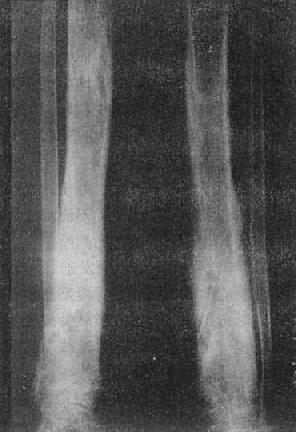

图2-1-9 骨盆骨质软化一骨软化症骨盆骨质密度普遍降低,骨皮质变薄、模糊,

骨小梁不清,骨盆有明显变形。耻骨支可见假骨折,呈光滑的透明线影,两侧对称